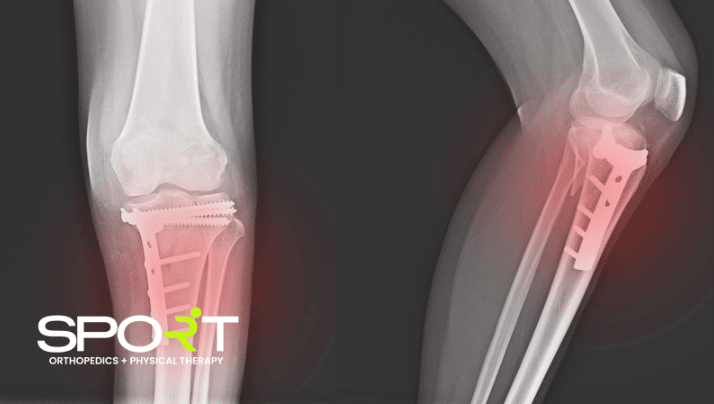

Knee fractures can cause extreme pain, especially during a hard fall. Injuries become easier to reoccur when other factors are combined with a hard fall, like osteoarthritis.